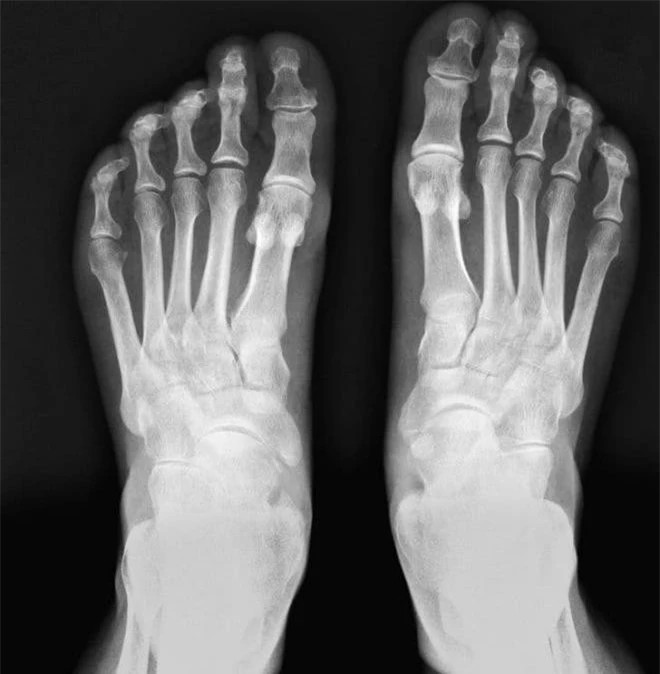

25% xương của một người trưởng thành nằm ở bàn chân của họ

Nó là một bộ phận nhỏ trên cơ thể, nhưng có tầm quan trọng lớn, mỗi bàn chân của chúng ta chứa 26 xương và hơn 100 cơ, gân và dây chằng. Ngay cả xương nhỏ nhất trên bàn chân của bạn cũng có thể nâng đỡ cơ thể, tạo ra sự ổn định và cân bằng.